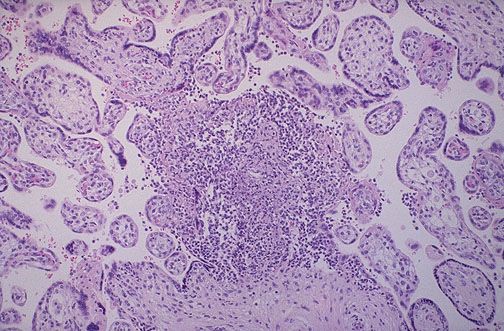

| Placental villitis is shown here with a small microabscess containing mostly neutrophils in a case of congenital infection with Listeria monocytogenes. Listeriosis is generally not life-threatening to the mother, but is potentially a cause for fetal demise. |